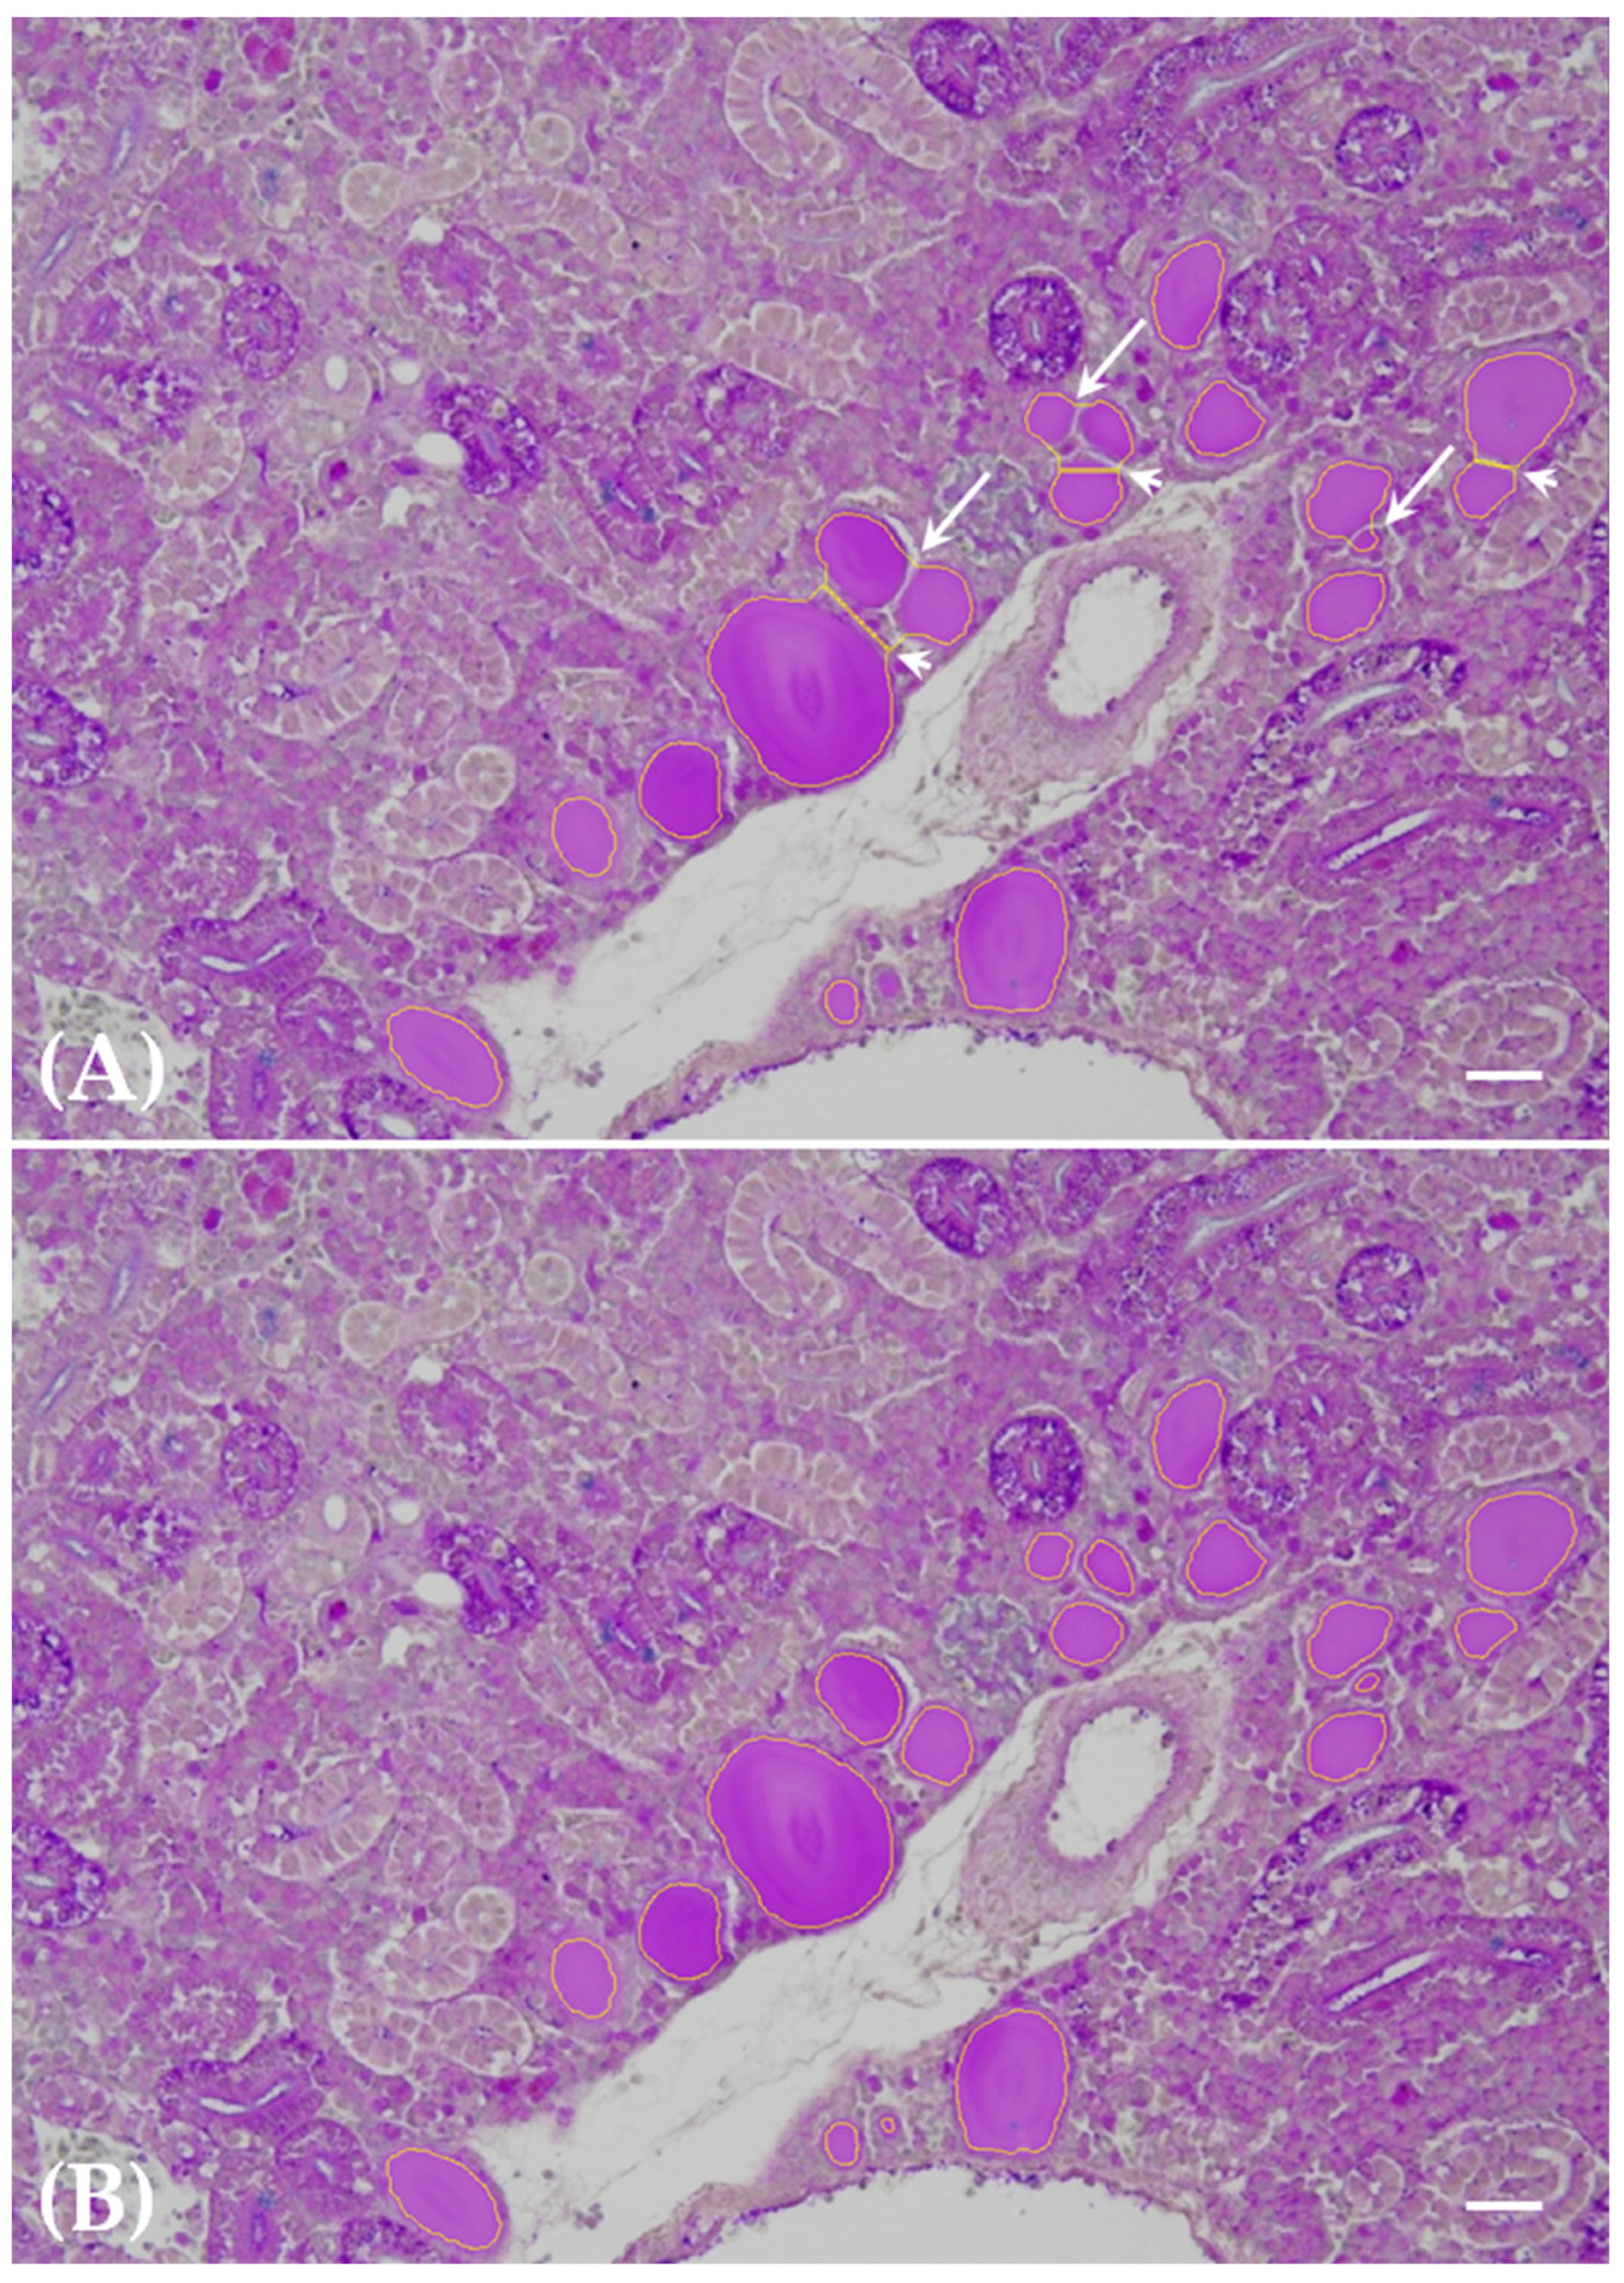

3.2. Thyroid Follicle Colloid Segmentation